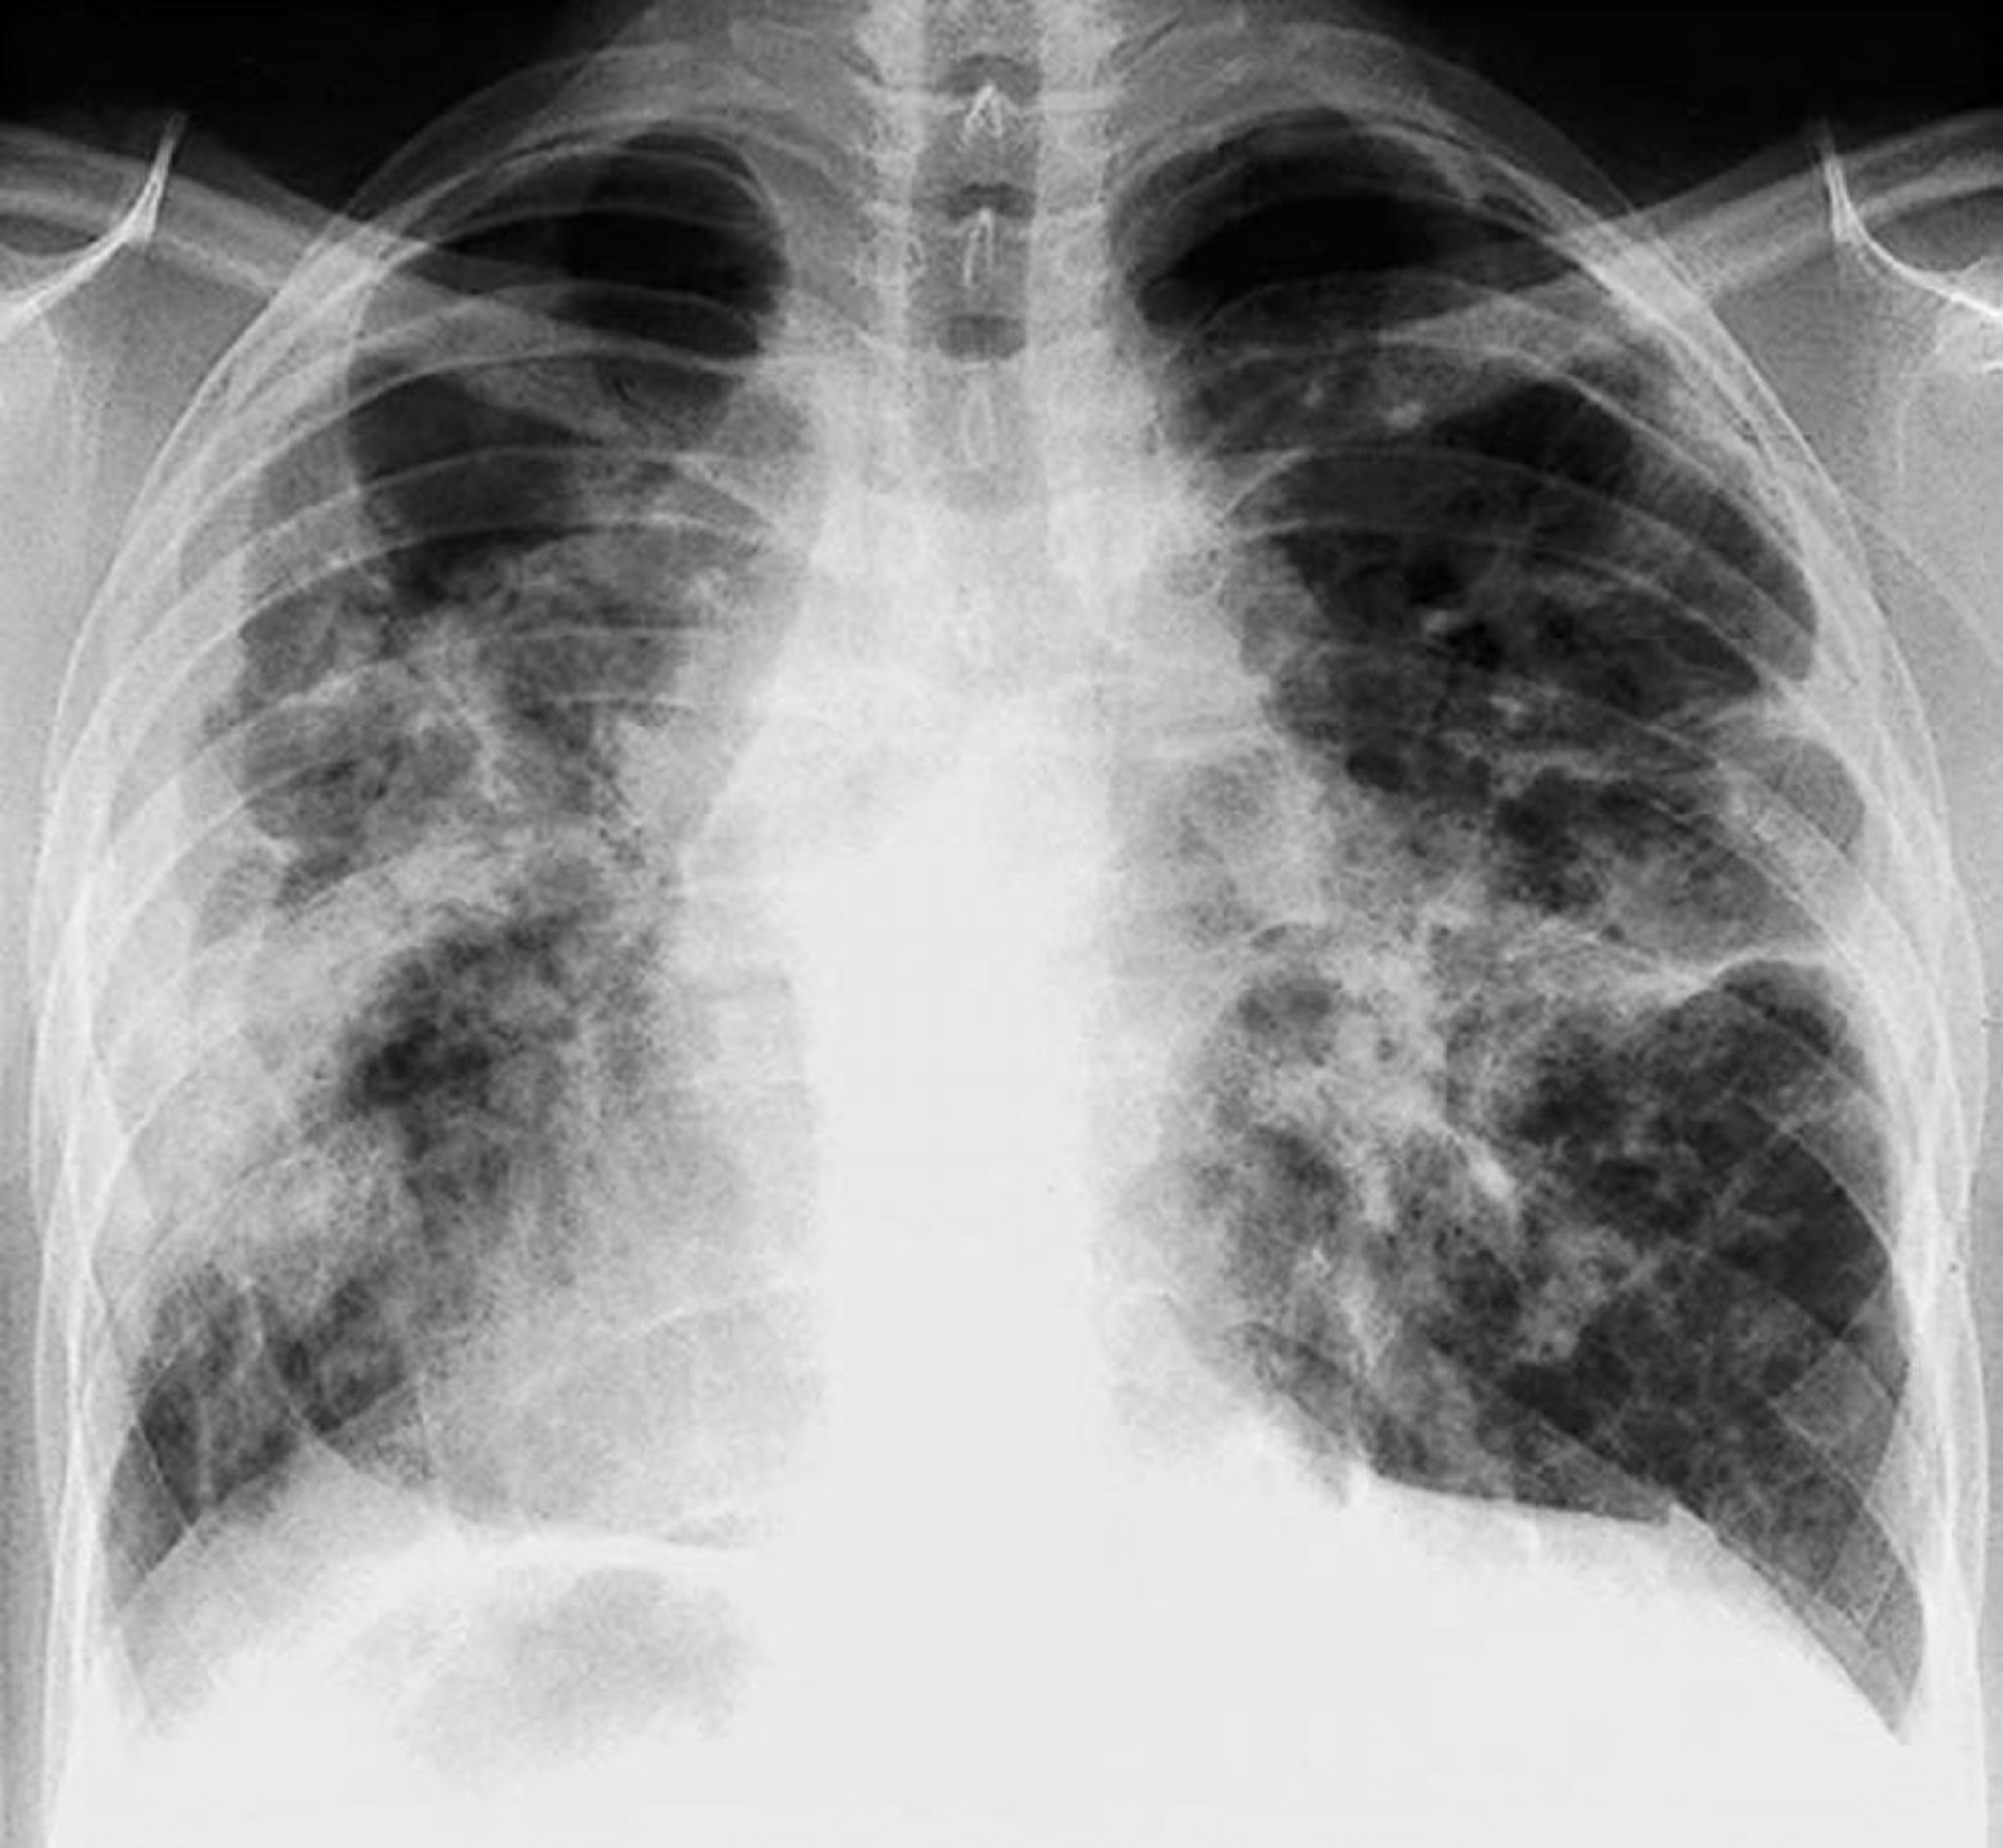

Sarcoidosis (estadio IV)

Fibrosis difusa grave con adenopatía hiliar y cambios quísticos de los lóbulos superiores en el estadio IV de la sarcoidosis.